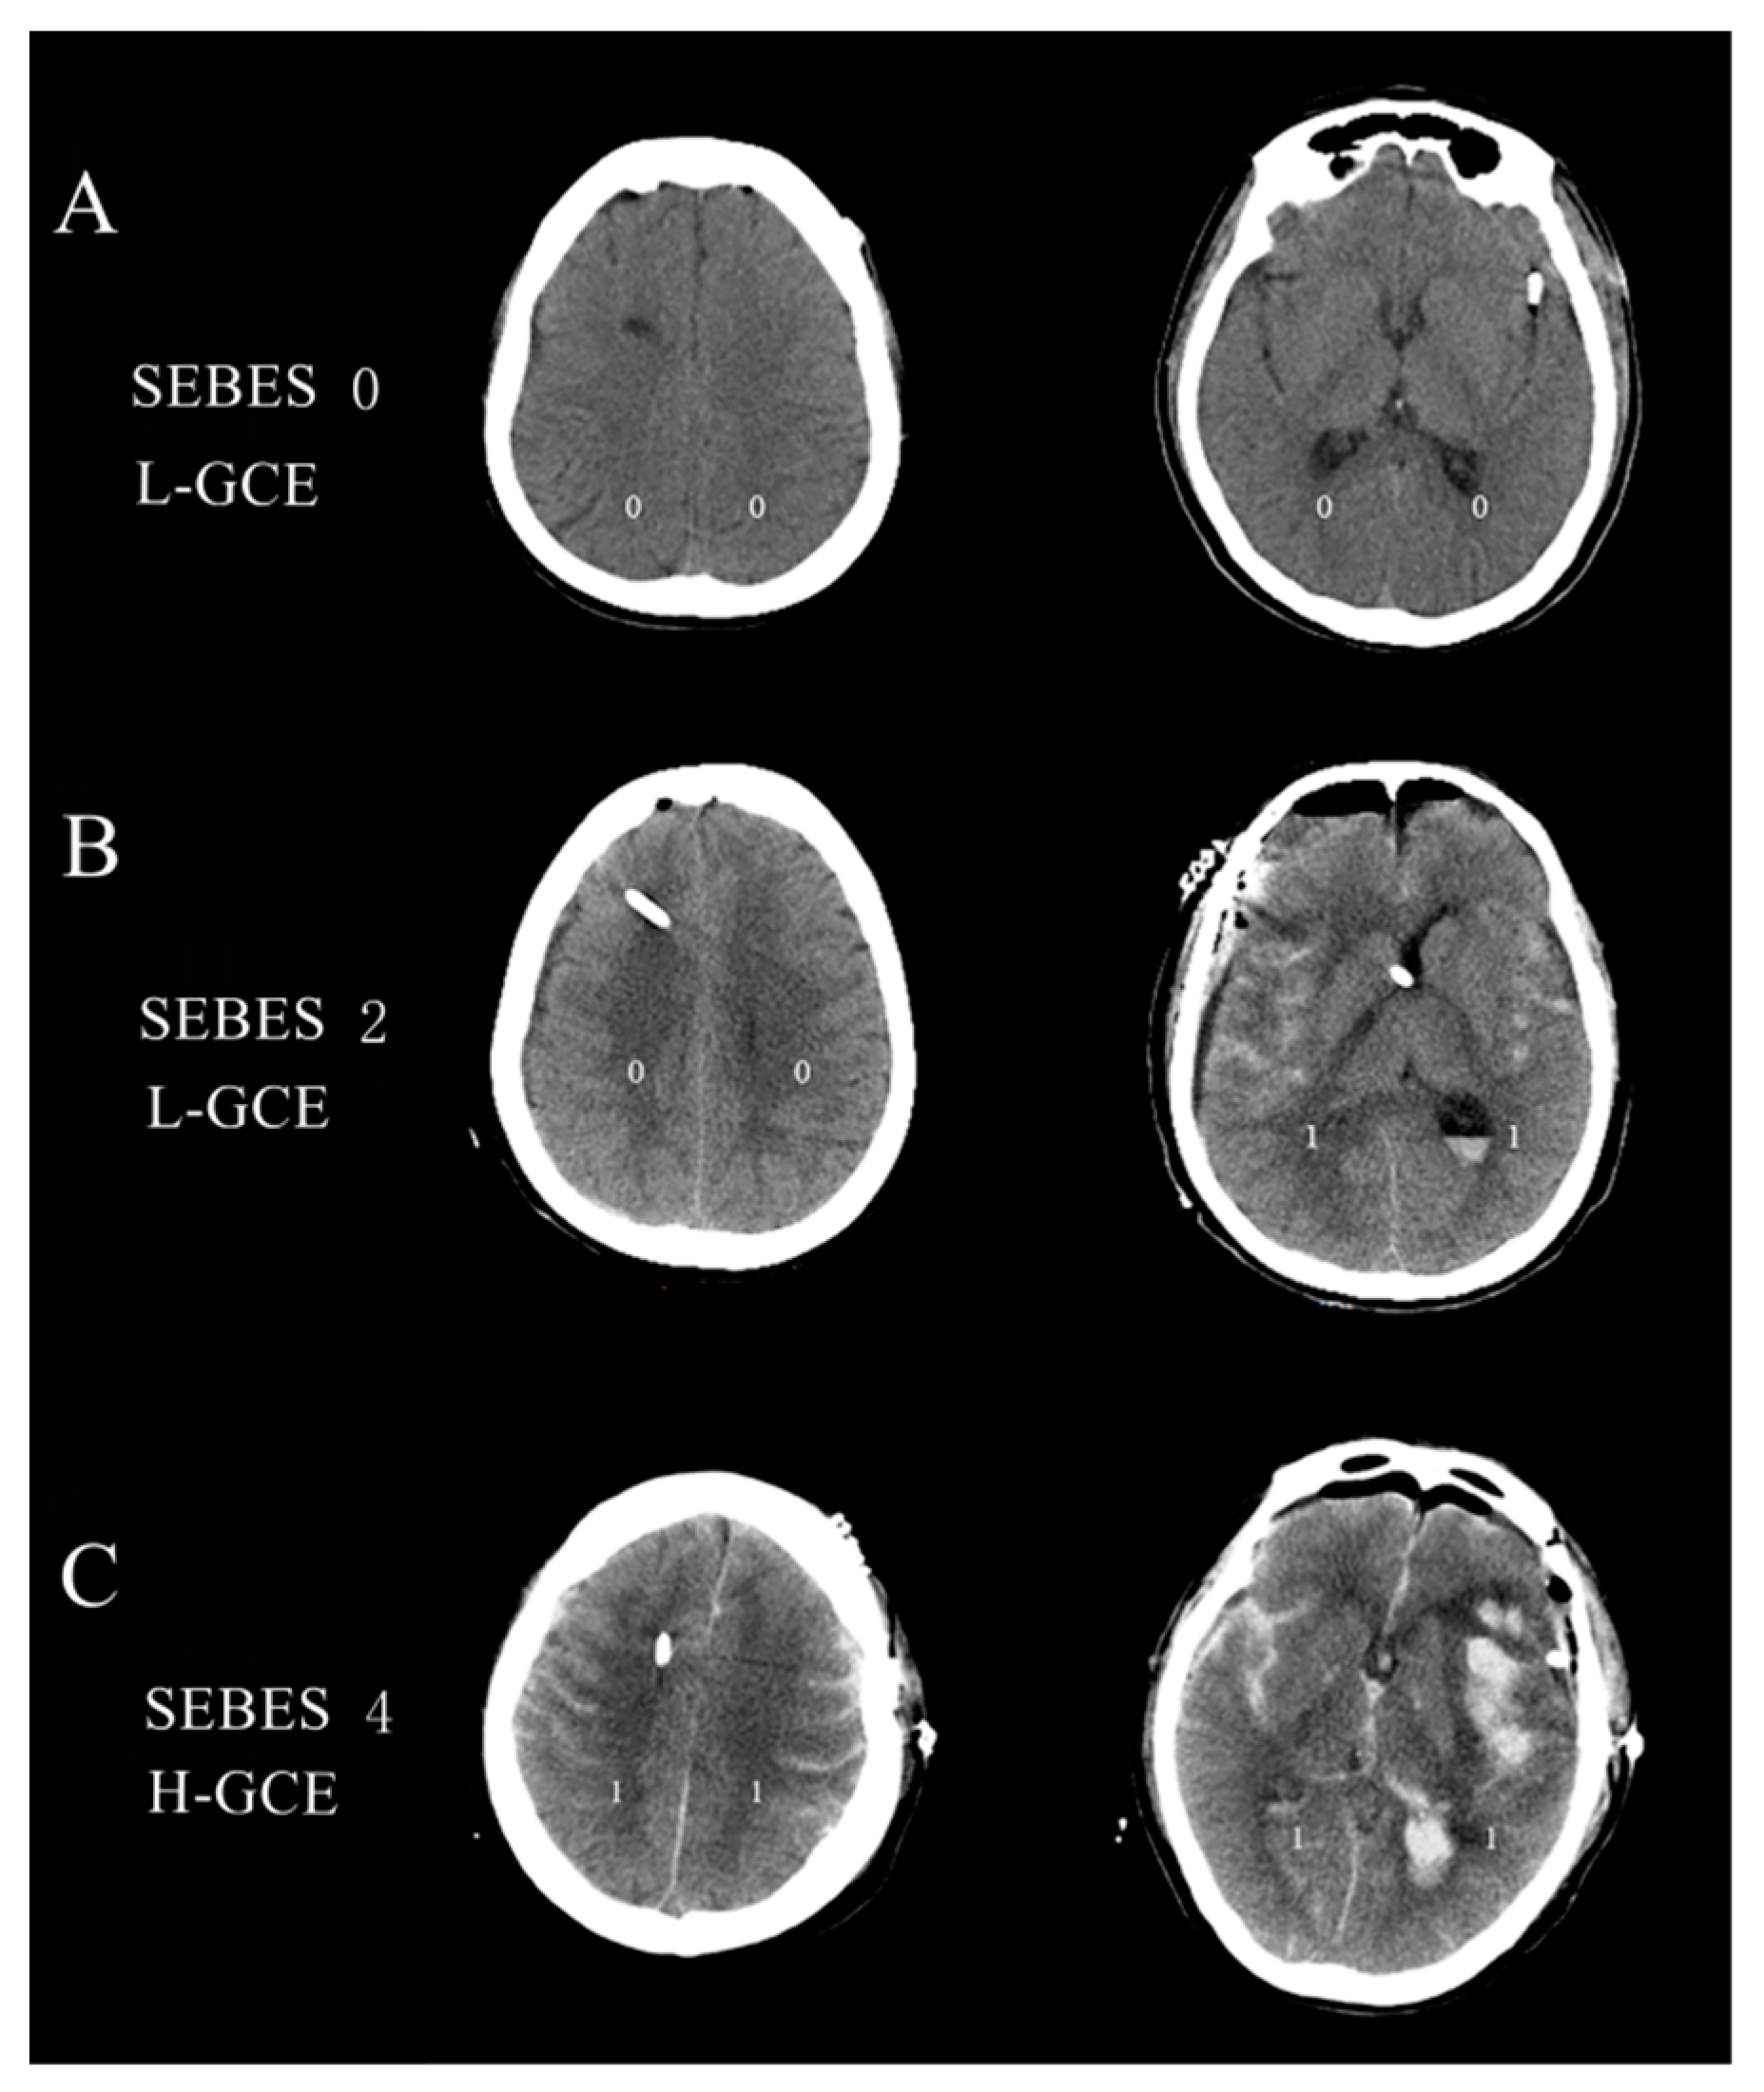

- Ahn, S.H.; Savarraj, J.P.; Pervez, M.; Jones, W.; Park, J.; Jeon, S.B.; Kwon, S.U.; Chang, T.R.; Lee, K.; Kim, D.H.; et al. The Subarachnoid Hemorrhage Early Brain Edema Score Predicts Delayed Cerebral Ischemia and Clinical Outcomes. Neurosurgery 2018, 83, 137–145. [Google Scholar] [CrossRef]

- Eibach, M.; Won, S.Y.; Bruder, M.; Keil, F.; Herrmann, E.; Berkefeld, J.; Seifert, V.; Konczalla, J. Age dependency and modification of the Subarachnoid Hemorrhage Early Brain Edema Score. J. Neurosurg. 2020, 134, 946–952. [Google Scholar] [CrossRef] [PubMed]